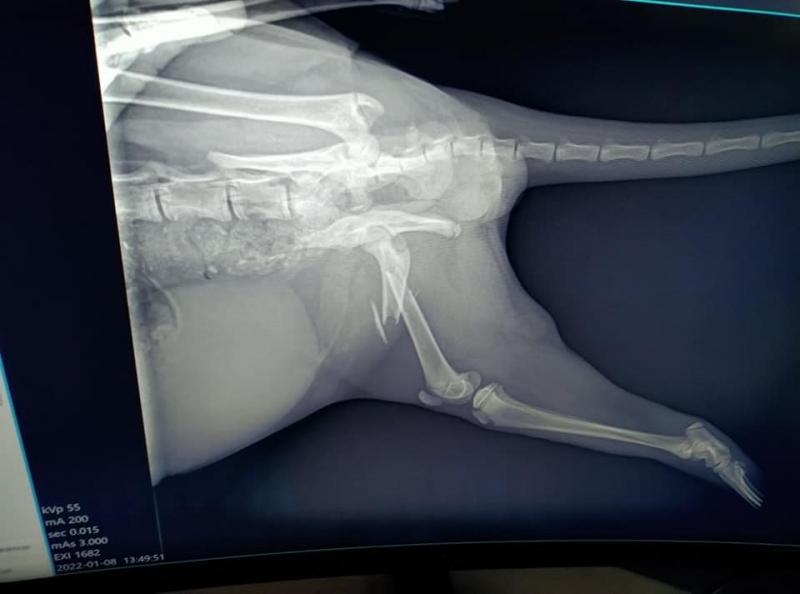

Котето има две спуквания на таза, строшен заден крайник и не може да върви. Нуждае се от незабавна интервенция и слагане на имплант, с цел да може да проходи, в противоположен случай това ще бъде невероятно, потвърдиха за Trafficnews от клиниката на доктор Капашиков.

Интервенцията би трябвало да бъде осъществена допустимо най-скоро, подари болките, които котето изпитва. Сумата за интервенцията възлиза близо 1100 лева, което включва престой в клиниката, анестезия, системи, медикаменти и самия имплант.